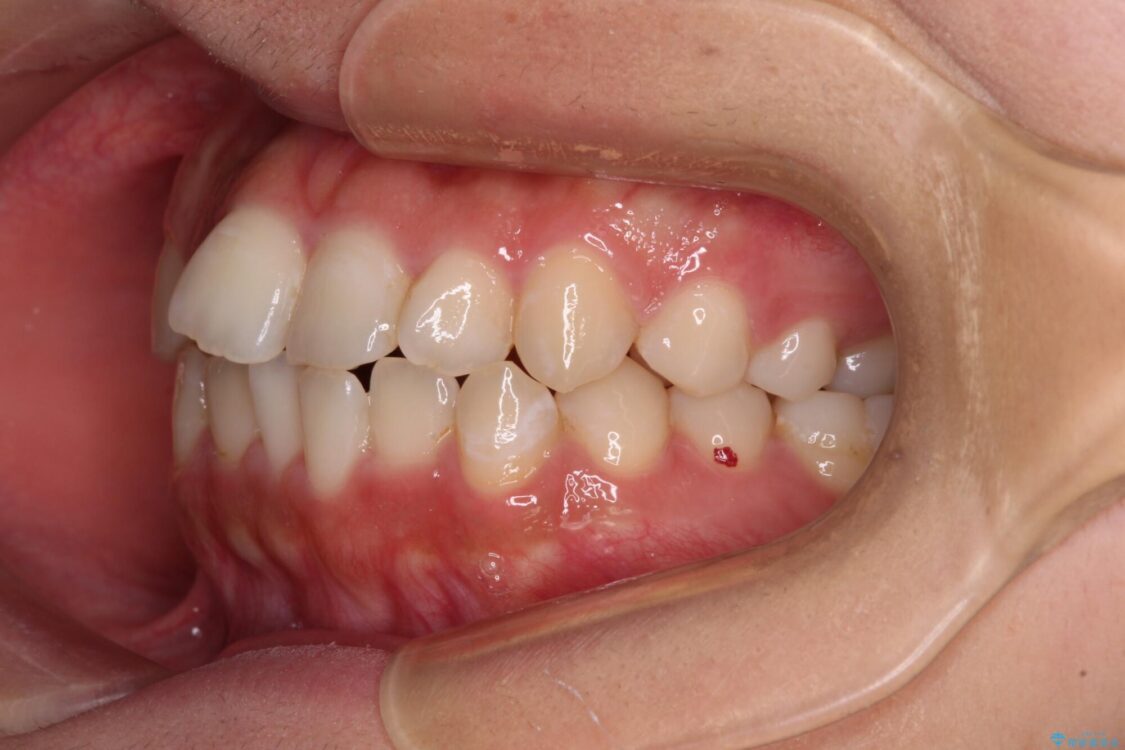

前歯のデコボコを気にして来院された患者様です。

治療前

• 【モニター】短期間で終わりたい ワイヤー装置での非抜歯矯正 治療前画像